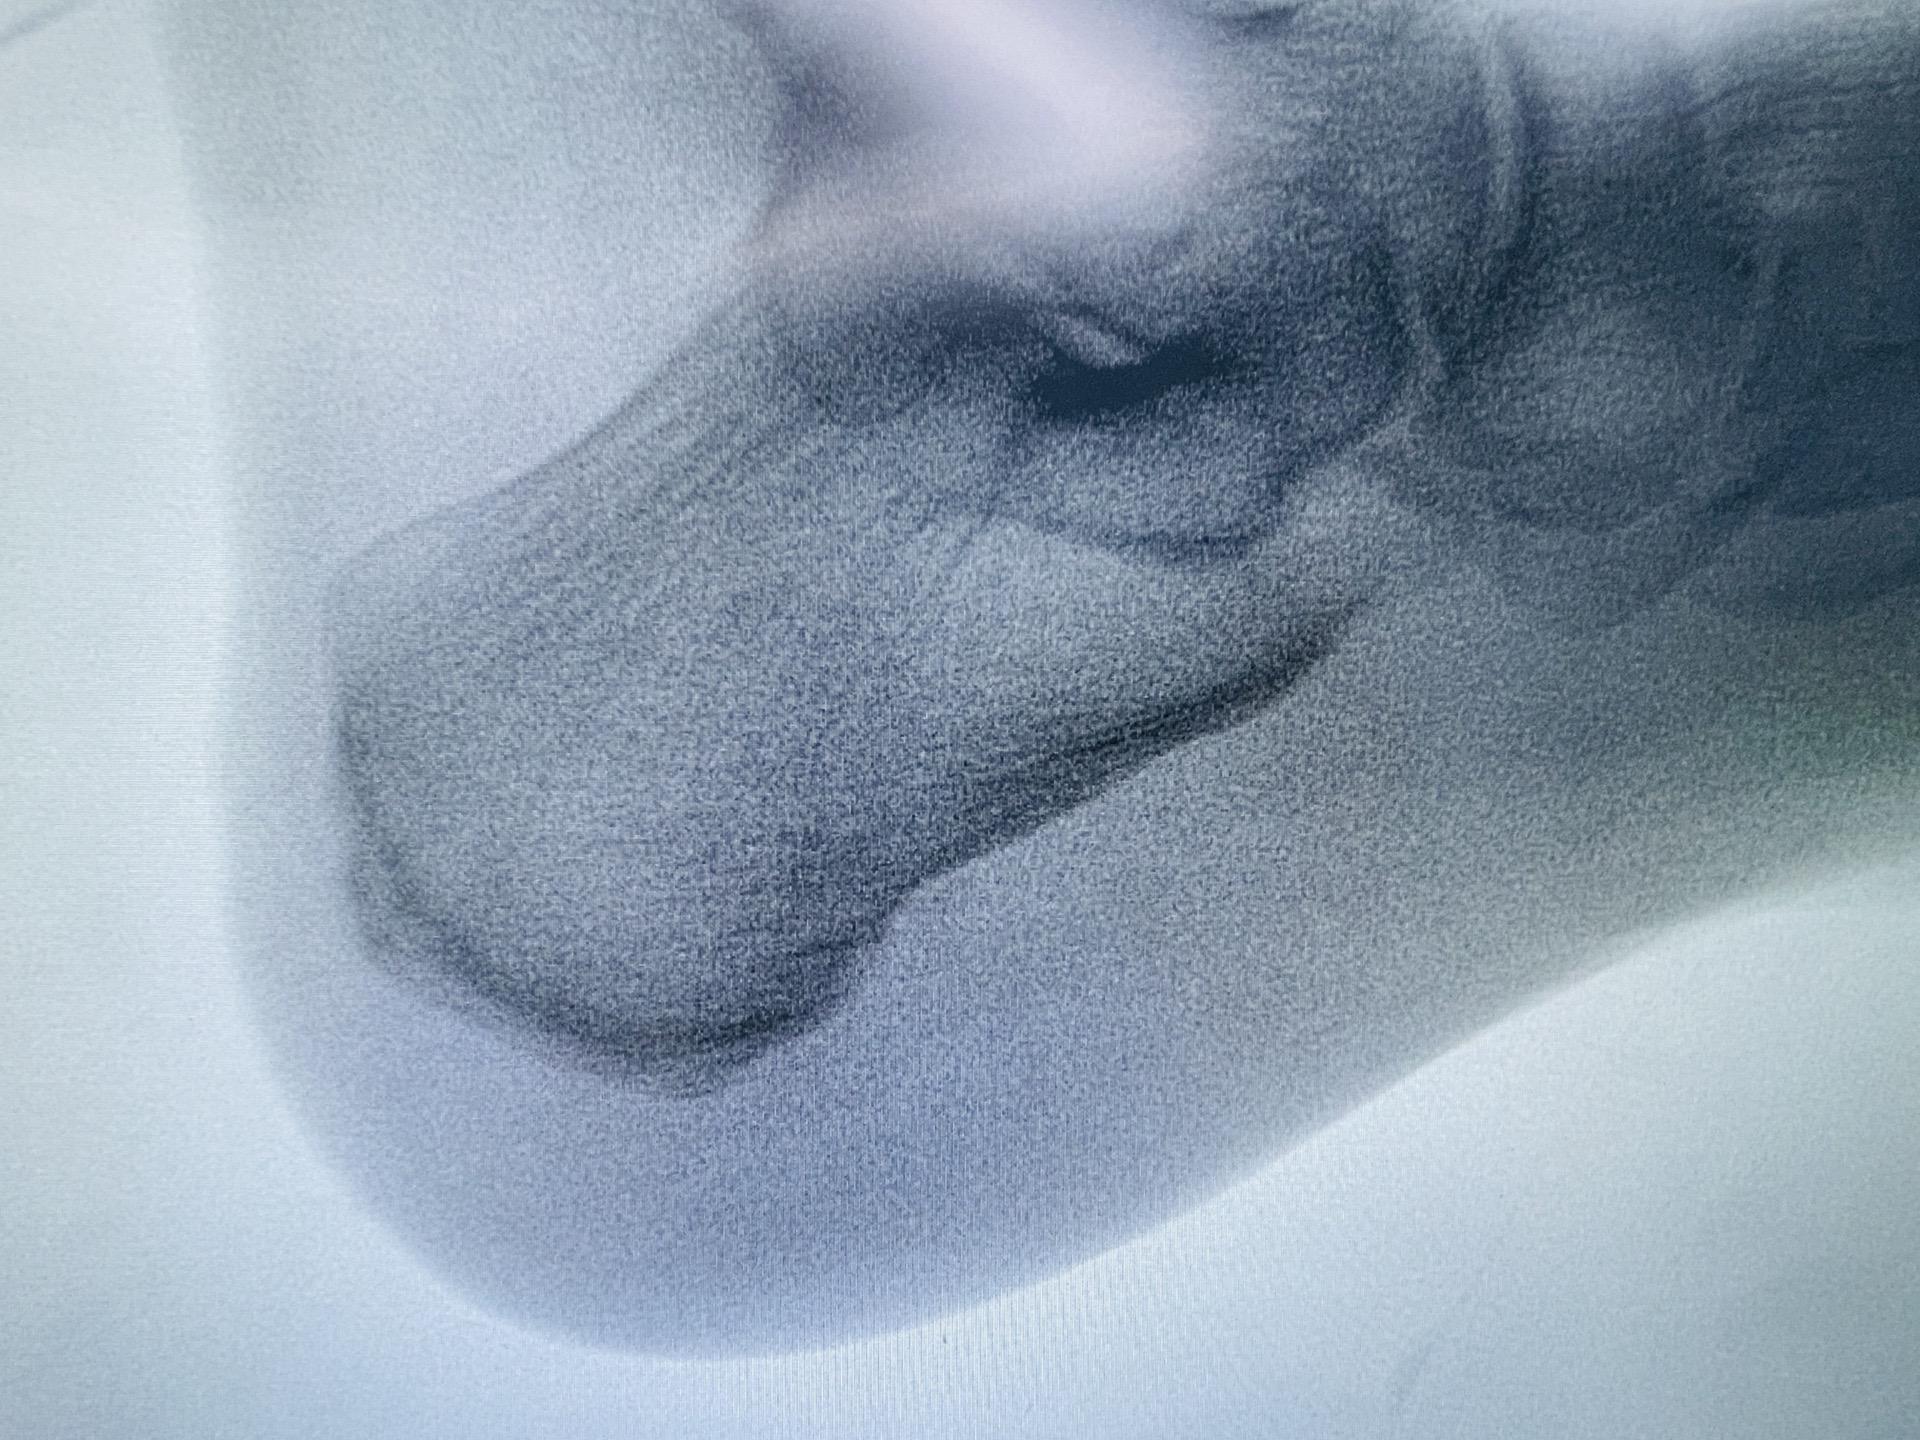

重获轻盈步伐。—— 关节镜下骨刺去除和跖筋膜松解术。医生通过两个小切口,使用关节镜精确地去除骨刺,并松解紧绷的跖筋膜。